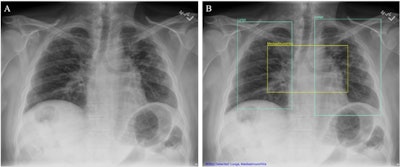

(A) Chest x-ray unaided by the AI system. (B) Chest x-ray aided by the AI system shows two Lung ROIs (green boxes) and a Mediastinum/Hila ROI (yellow box). The AI system identified abnormalities that were characterized as regions of interest in Lungs and Mediastinum/Hila. The abnormalities were bilateral upper lobe pulmonary fibrosis (categorized as ‘Lungs’), and pulmonary artery hypertension along with bilateral hilar retraction (categorized as ‘Mediastinum/Hila’). The ROIs for each category are illustrated in different colors for readability.Image available for republishing under Creative Commons license (CC BY 4.0 DEED, Attribution 4.0 International) and courtesy of Scientific Reports.